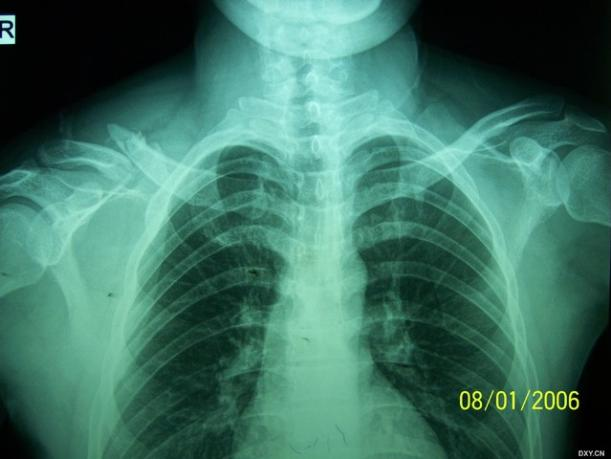

肩关节脱位合并大结节撕脱骨折在临床非常常见,通过我们的各种复位手法复位后是不是效果都非常好?一般在肩关节脱位纠正后大结节撕脱骨折也多自行复位了。

都这么简单吗?还真不一定,如果让你遇到了肩关节脱位合并隐匿性骨折就是一个巨大的坑了。看看下面的病例:

看片子似乎是一个简单的肩关节脱位并大结节撕脱骨折。

整复后拍片复查却成这个样子了……

其实这种往往都是合并了肱骨颈部隐匿性骨折。

临床上还真不罕见,只要遇到一例绝对让你头大如斗,因为骨折移位合并脱位处理起来极为麻烦,一般都预后欠佳。